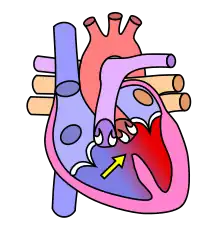

Dans le cœur normal, la cloison qui sépare les ventricules droit et gauche, dénommée « septum interventriculaire », est totalement hermétique. Une CIV correspond à la présence d'un orifice plus ou moins large dans cette cloison, permettant le passage direct du sang d'un ventricule à l'autre. Les conséquences de cette malformation dépendent essentiellement de la taille de la communication. Dans la plupart des cas, l'orifice est petit : ces CIV sans conséquence réellement gênante sont appelées « maladie de Roger ». L'évolution d'une CIV dépend de sa localisation sur le septum, certaines étant susceptibles de se fermer spontanément dans les mois ou années suivant la naissance.

Différentes localisations des CIV

La complexité de la formation embryologique de la cloison interventriculaire, nécessitant l'alignement et la fusion de quatre constituants explique, au moins en partie, la fréquence des CIV.

Connaître non seulement la taille mais aussi la localisation d'une CIV a un double intérêt :

- C'est le cas des CIV qui siègent dans le septum d'admission (partie 1 en rouge sur le schéma), fréquemment associée à une Trisomie 21, et de celles qui siègent dans le septum sous-aortique (partie 4 en bleu sur le schéma), parfois associées à une anomalie du chromosome 22 (Microdélétion 22q11) ;

- les CIV siégeant dans le septum membraneux (partie 3 en jaune sur le schéma) et encore plus les CIV musculaires situées dans la partie 2 (en vert sur le schéma) sont fréquemment capables de « se guérir toutes seules » (à condition que l'état de l'enfant permette d'attendre).

- les CIV situées dans les parties 1 (septum d'admission) et 4 (septum sous-aortique) ne se ferment jamais spontanément et devront donc, sauf exception, être opérées tôt ou tard.

Schéma sur les localisations des communications interventriculaires (légende) :

- CIV membraneuse et péri-membraneuse (1-2-3)

- CIV d'admission ou postérieure (4)

- CIV musculaire ou trabéculée (5-6)

- CIV sous-aortique (7)

- CIV infundibulaire (8).